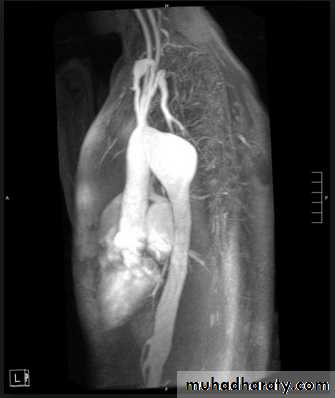

Sarcoid.

Marked lymphadenopathy (dotted lines) is seen in the region of both hila in the right paratracheal region (A).

The transverse contrast-enhanced computed tomography scan of the upper chest (B) clearly shows the ascending and descending aorta (Ao) as well as the pulmonary artery (PA) and superior vena cava. The right and left main-stem bronchus area also is seen. Arrows, the extensive lymphadenopathy.